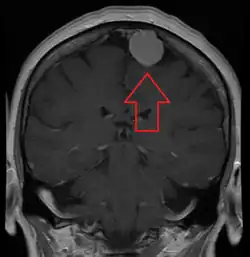

![]() | |

| An MRI of the brain, demonstrating the appearance of a meningioma | |

Meningiomas are visualized readily with contrast CT, MRI with gadolinium,[23] and arteriography, all attributed to the fact that meningiomas are extra-axial and vascularized. CSF protein levels are usually found to be elevated when lumbar puncture is used to obtain spinal fluid. On T1-weighted contrast-enhanced MRI, they may show a typical dural tail sign absent in some rare forms of meningiomas.[18]